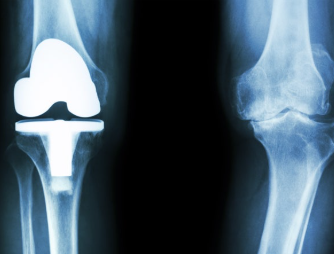

1. 무릎 인공관절 수술이란?

무릎 인공관절 수술은 퇴행성 관절염이나 관절 손상으로 인해 정상적인 생활이 어려운 분들을 위해 손상된 관절을 금속 또는 플라스틱 인공관절로 치환하는 수술입니다.

- 일반적으로 치환술이라고도 하며, 전치환(전체 교체)과 부분 치환술로 나뉩니다.